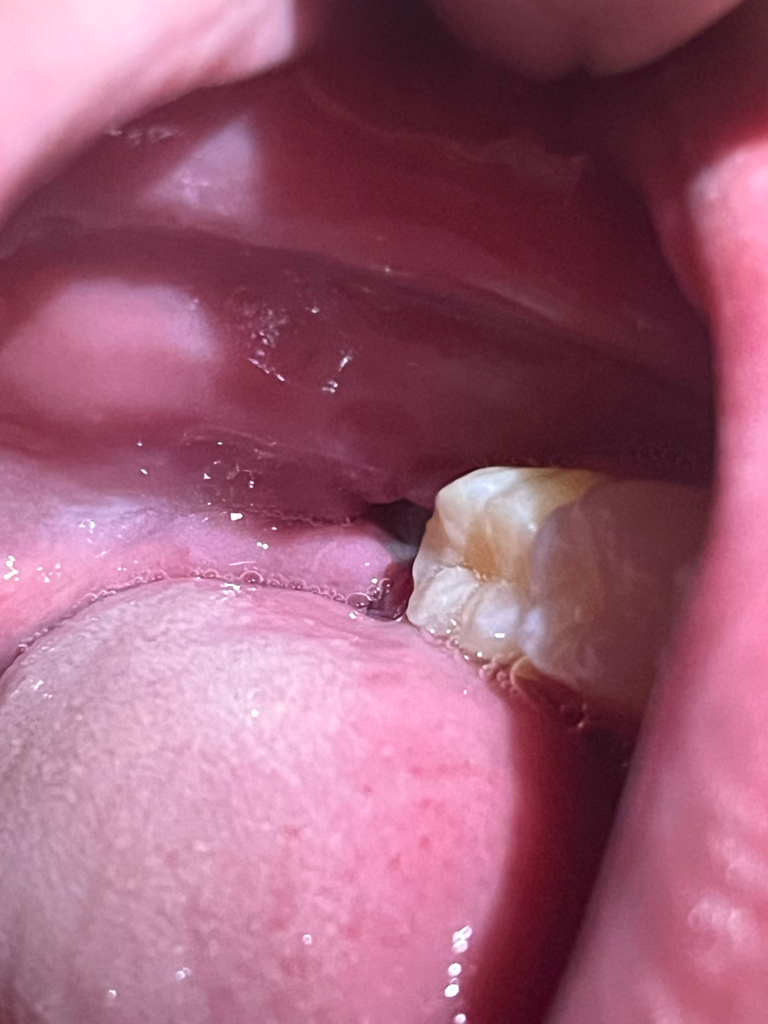

사랑니 위,아래 발치를 하고 정확히 7일 뒤 다시 병원가서 실밥 제거를 위해 방문 했습니다. 근데 의사인지 쨋든 그 분이 하는 말이 실밥이 살짝 벌어져 그 사이로 음식물이 끼여서 소독 후 다시 재봉합을 한다고 하여 봉합을 했는데 봉합 후에도 뭔가 잘 안되지 않았는지 일단 잘 아물기 위해서는 식사 후 위생관리 잘 하라며 마지막에 거즈를 물려 주셨어요 그리고 재봉합 후 2일되는 저녁에 뭔가 공간이 생기고 아주 사알짝 불편함과 동시에 시림?이 느껴지든데 실밥이 풀린건지 만약 풀렸다면 현재 사랑니 발치 후 10일이상이 지나고있는데 다시 봉합을 해야되는지 몰라서 질문 합니다.

일단 사진상에서는 봉합실이 보이진 않습니다 발치 부위 잇몸 조금 벌어져 있더라도 큰 문제는 없습니다 다만 음식물이 잘 끼게 되므로 빈 주사기 등으로 낀 음식물을 잘 빼주는 등 관리를 잘해주어야 합니다